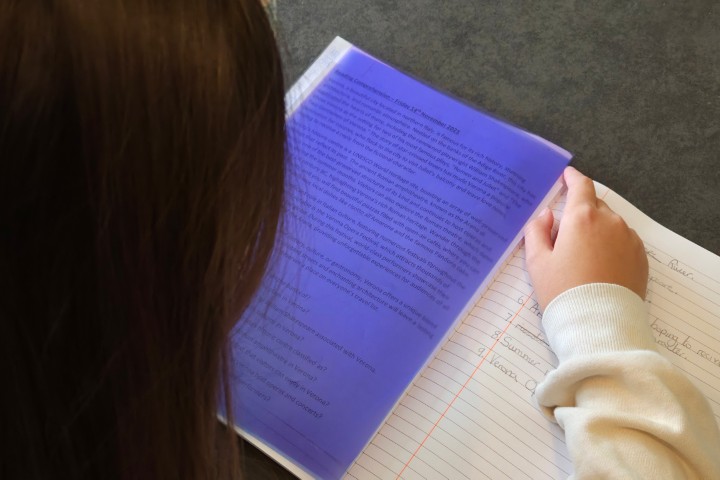

Swirled print distortion suffered by some people with visual perception processing problems

Individuals with Irlen syndrome will often complain of light sensitivity associated with sunlight, bright lighting, fluorescent lights, headlight and glare. They may also have reading problems, as reading becomes inefficient and they may need to re-read for comprehension or build breaks into reading. High contrast (black print on white paper) and visually-intensive activities, create high levels of stress for the brain that trigger physical symptoms which may include headaches and migraines. Brain imaging, both SPECT scans and fMRI, of individuals with this condition shows over-activity, complex brain patterns and non-normalised functioning. This results in a variety of issues, including difficulties reading because of a lack of print stability, issues with glare or discomfort from the white background on the printed page, problems with depth perception and physical symptoms, such as headaches, nausea, dizziness, brain fog, anxiety, strain and fatigue.